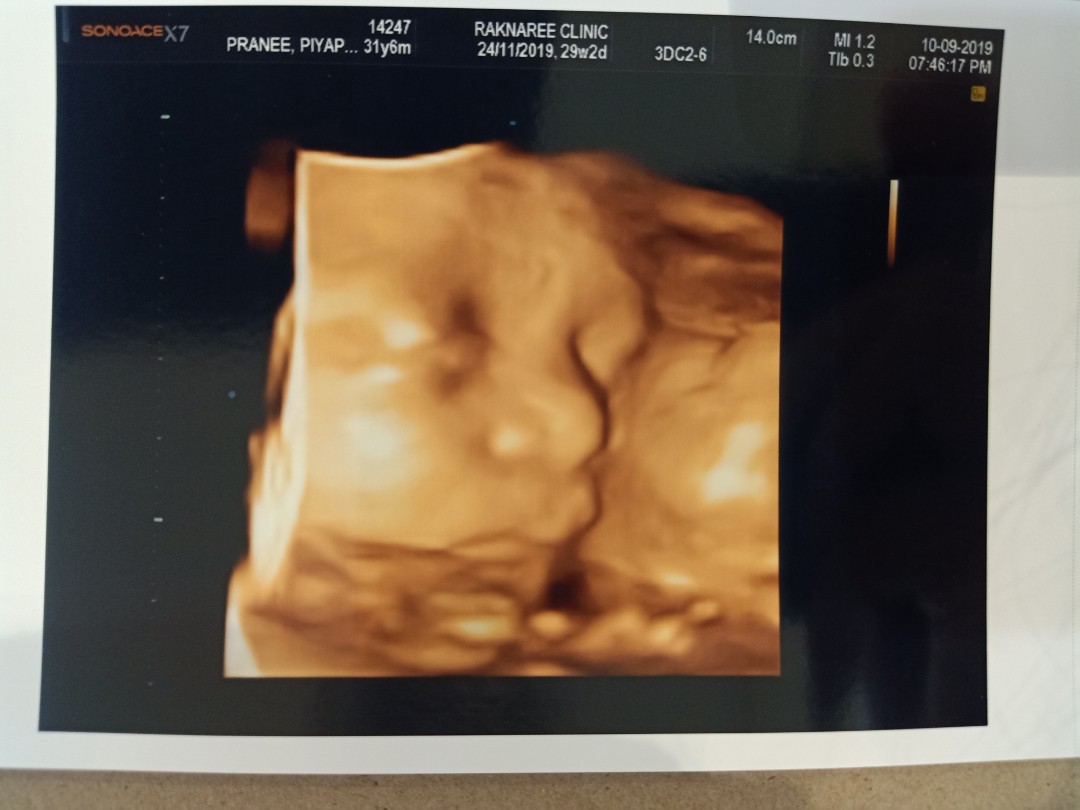

เอาเด็กชายปากคว่ำ เดือน พย. มาอวดจ้า

อายุครรถ์ 32วีค5วัน ผมหนัก 2,100 แล้วครับ ขอดูเด็กเดือน พย. น่ารักๆหน่อยครับ ผมไม่ชอบเลยเวลาคุณหมอซาวด์ หน้าจะบึ้งหน่อยๆ55555

แก้มเยอะจังลูก